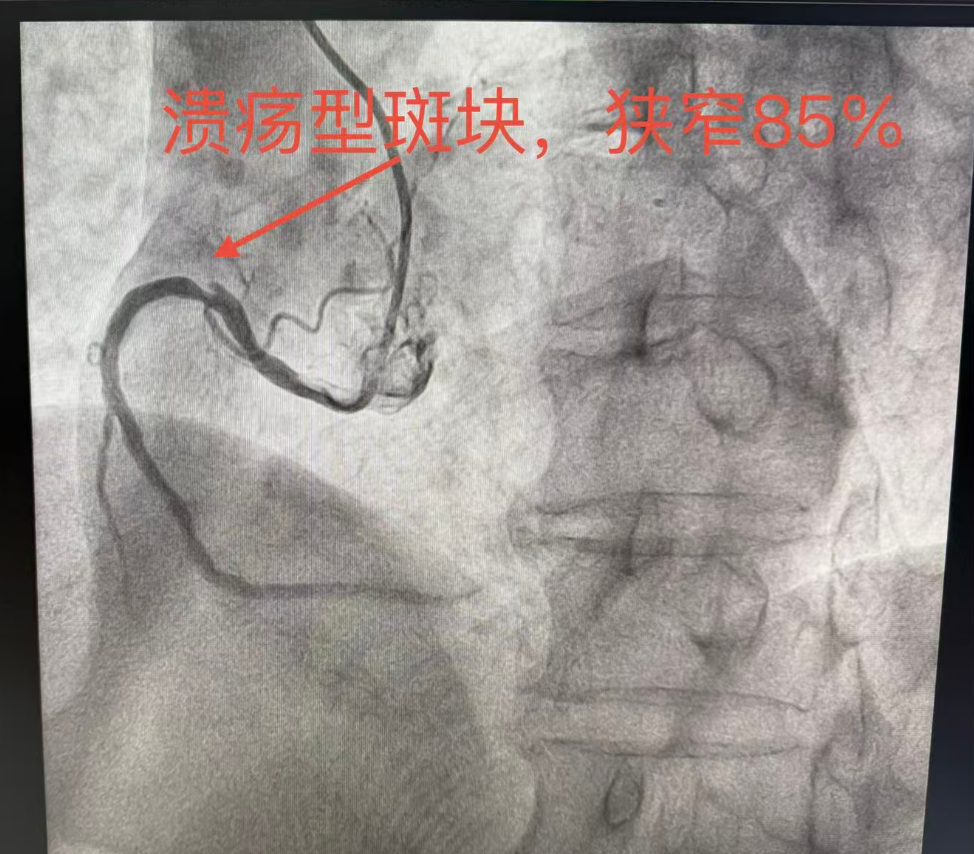

入院后,陕西冶金医院血管外科团队安排专科检查,结合症状与检查结果

结合症状与检查结果,明确诊断:1.右下肢大隐静脉曲张;2.右下肢大隐静脉瓣功能不全。

陕西冶金医院血管外科王玉德主任与党金鑫医生针对患者病情采用微创综合治疗。得益于微创术式的优势,术后李阿姨恢复速度远超预期,当天就可以下床正常活动,困扰她多年的腿部胀痛、酸胀不适感瞬间得到明显缓解,整个人的精神状态都好了很多。